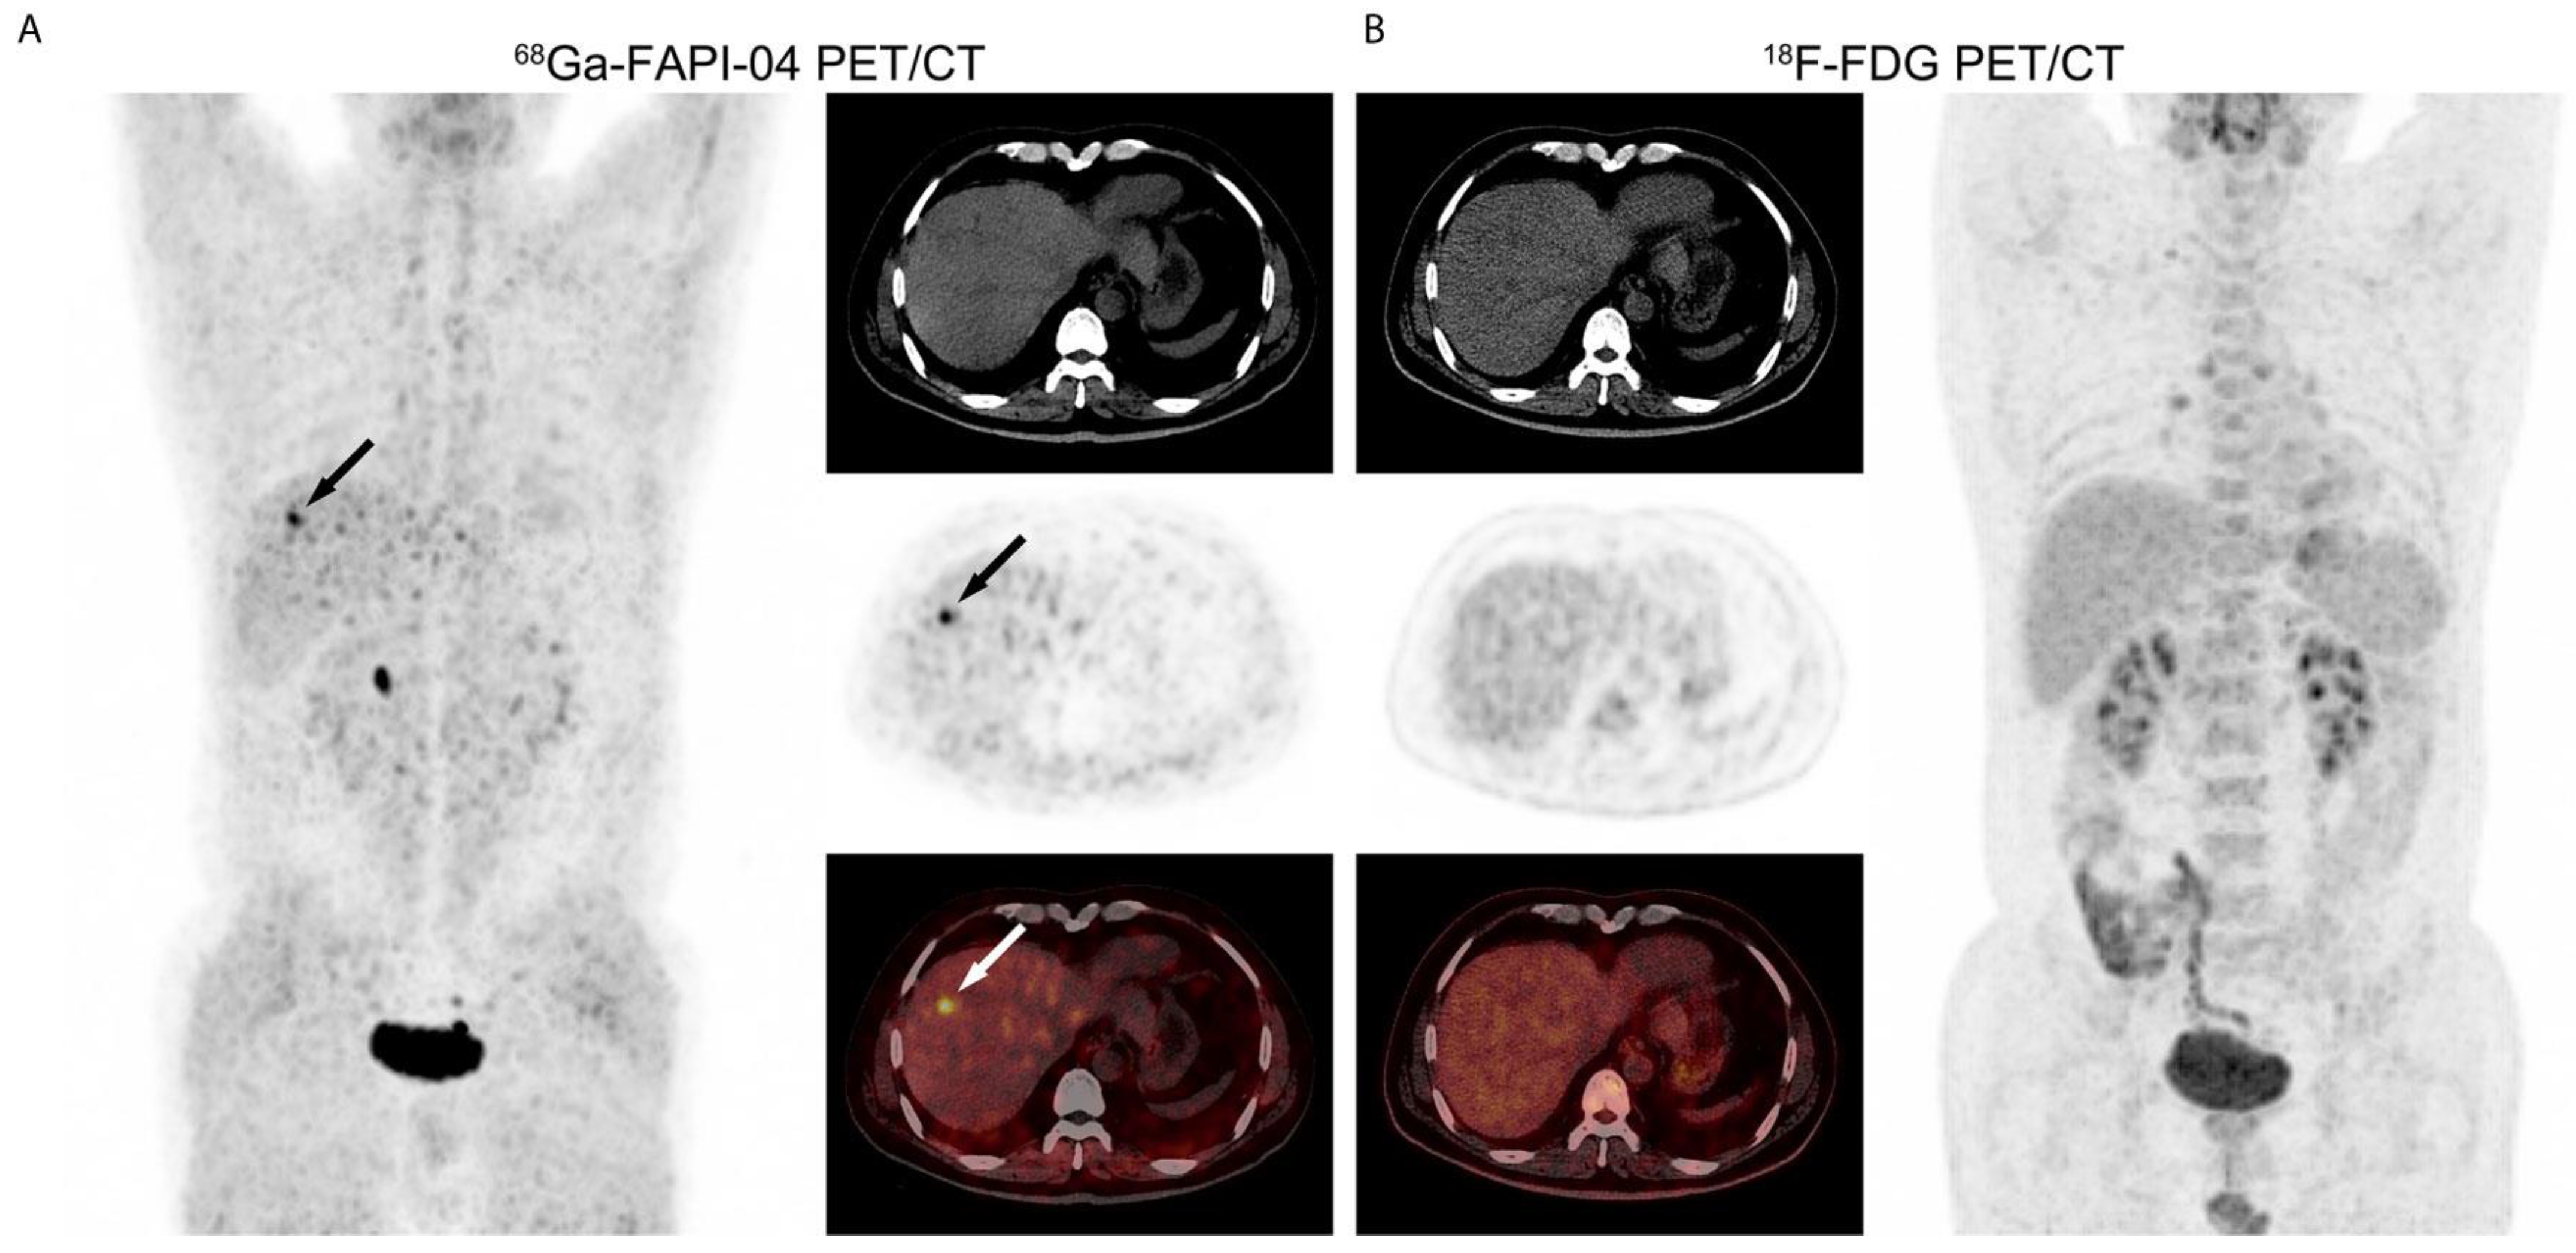

- Pabst, K.M.; Trajkovic-Arsic, M.; Cheung, P.F.Y.; Ballke, S.; Steiger, K.; Bartel, T.; Schaarschmidt, B.M.; Milosevic, A.; Seifert, R.; Nader, M.; et al. Superior Tumor Detection for 68Ga-FAPI-46 Versus 18F-FDG PET/CT and Conventional CT in Patients with Cholangiocarcinoma. J. Nucl. Med. 2023, 64, 1049–1055. [Google Scholar] [CrossRef] [PubMed]